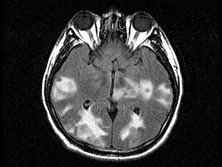

脑弓形体病

脑弓形体病是一种由刚性弓形体原虫引起的脑寄生虫病,是弓形体病死亡的主要原因。先天...